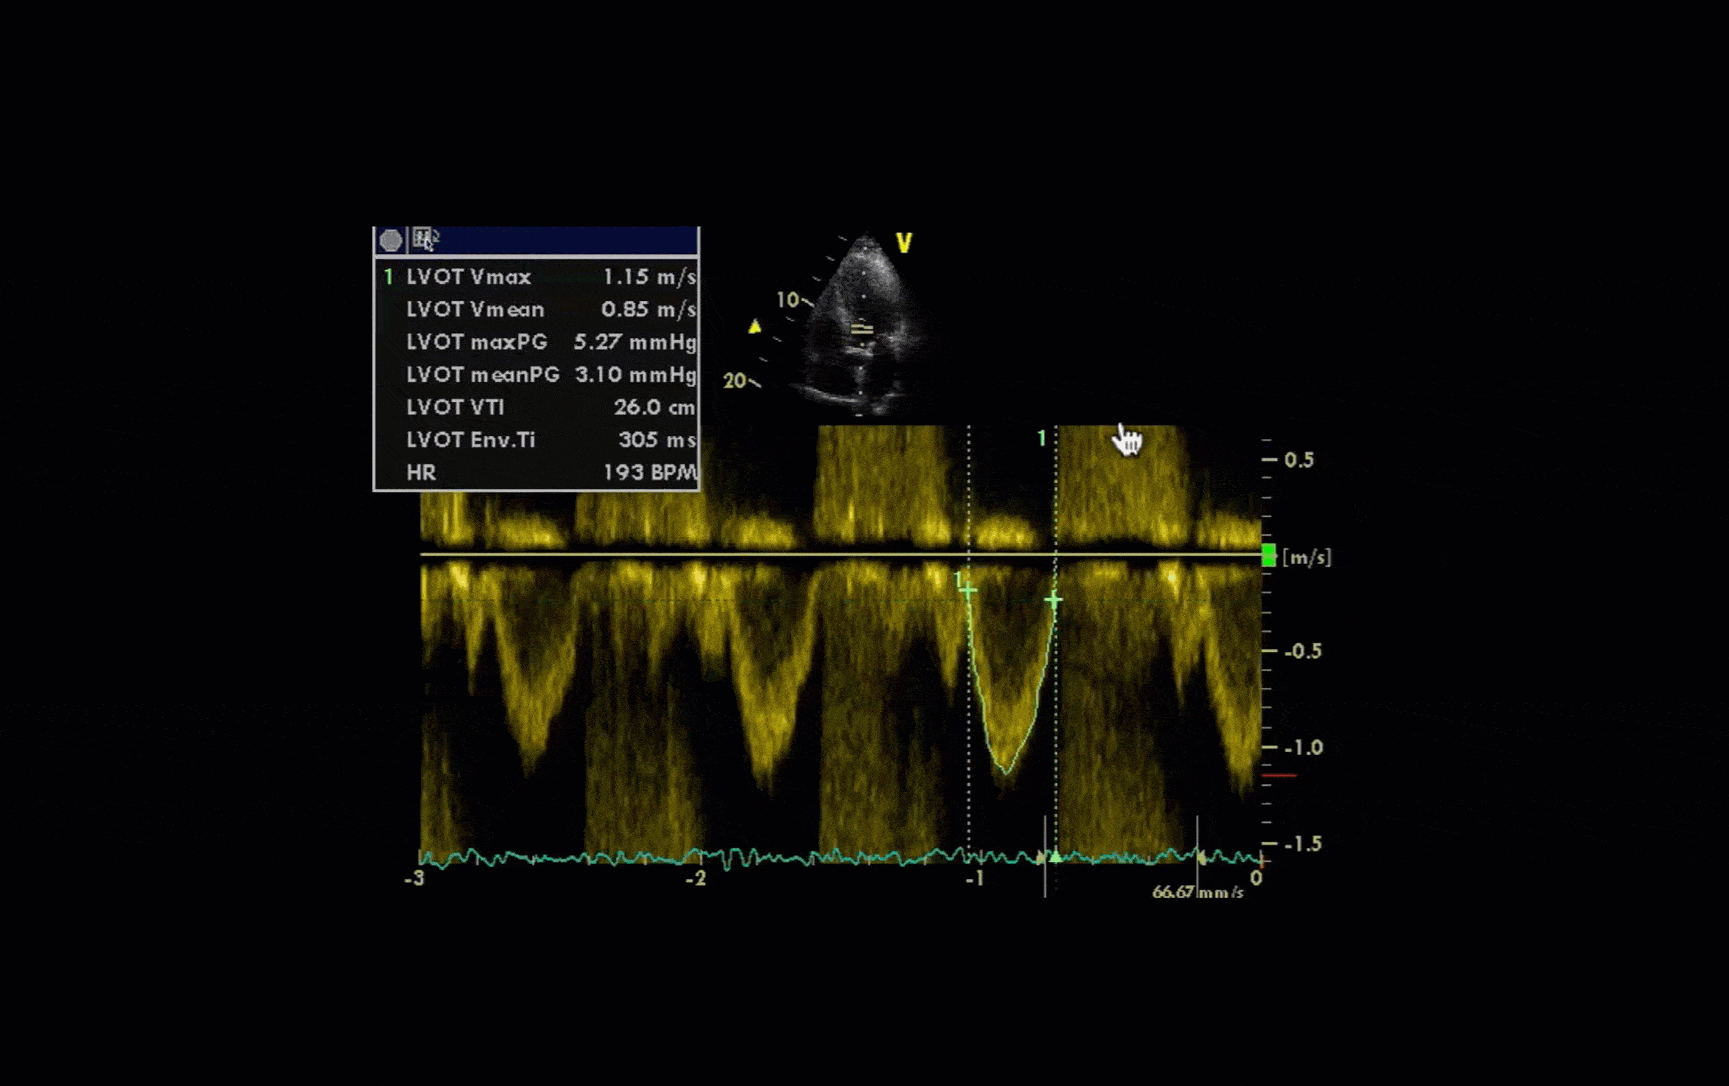

Pulsed wave Doppler example

So again, we’re now looking at a pulsed wave signal, and we can see that because we’ve got our little parallel lines there, showing us that that’s where we’re sampling from (we’re in the outflow tract of the left ventricle).

And it’s giving us this signal that you can see below (marked in green), that the hand icon is pointing to:

However, if you look below, there’s lots of what looks like a sort of crazy display.

And that’s because this patient has aortic regurgitation.

Pulsed wave Doppler can display signals up to about 1.5 metres per second. But if it goes over that, it has a problem: because it’s waiting to receive ultrasound before it sends the next signal out, it can’t sample the signal frequently enough to display it accurately. And then what you get is that rather confusing sort of wraparound signal, displaying velocities both above and below the line.